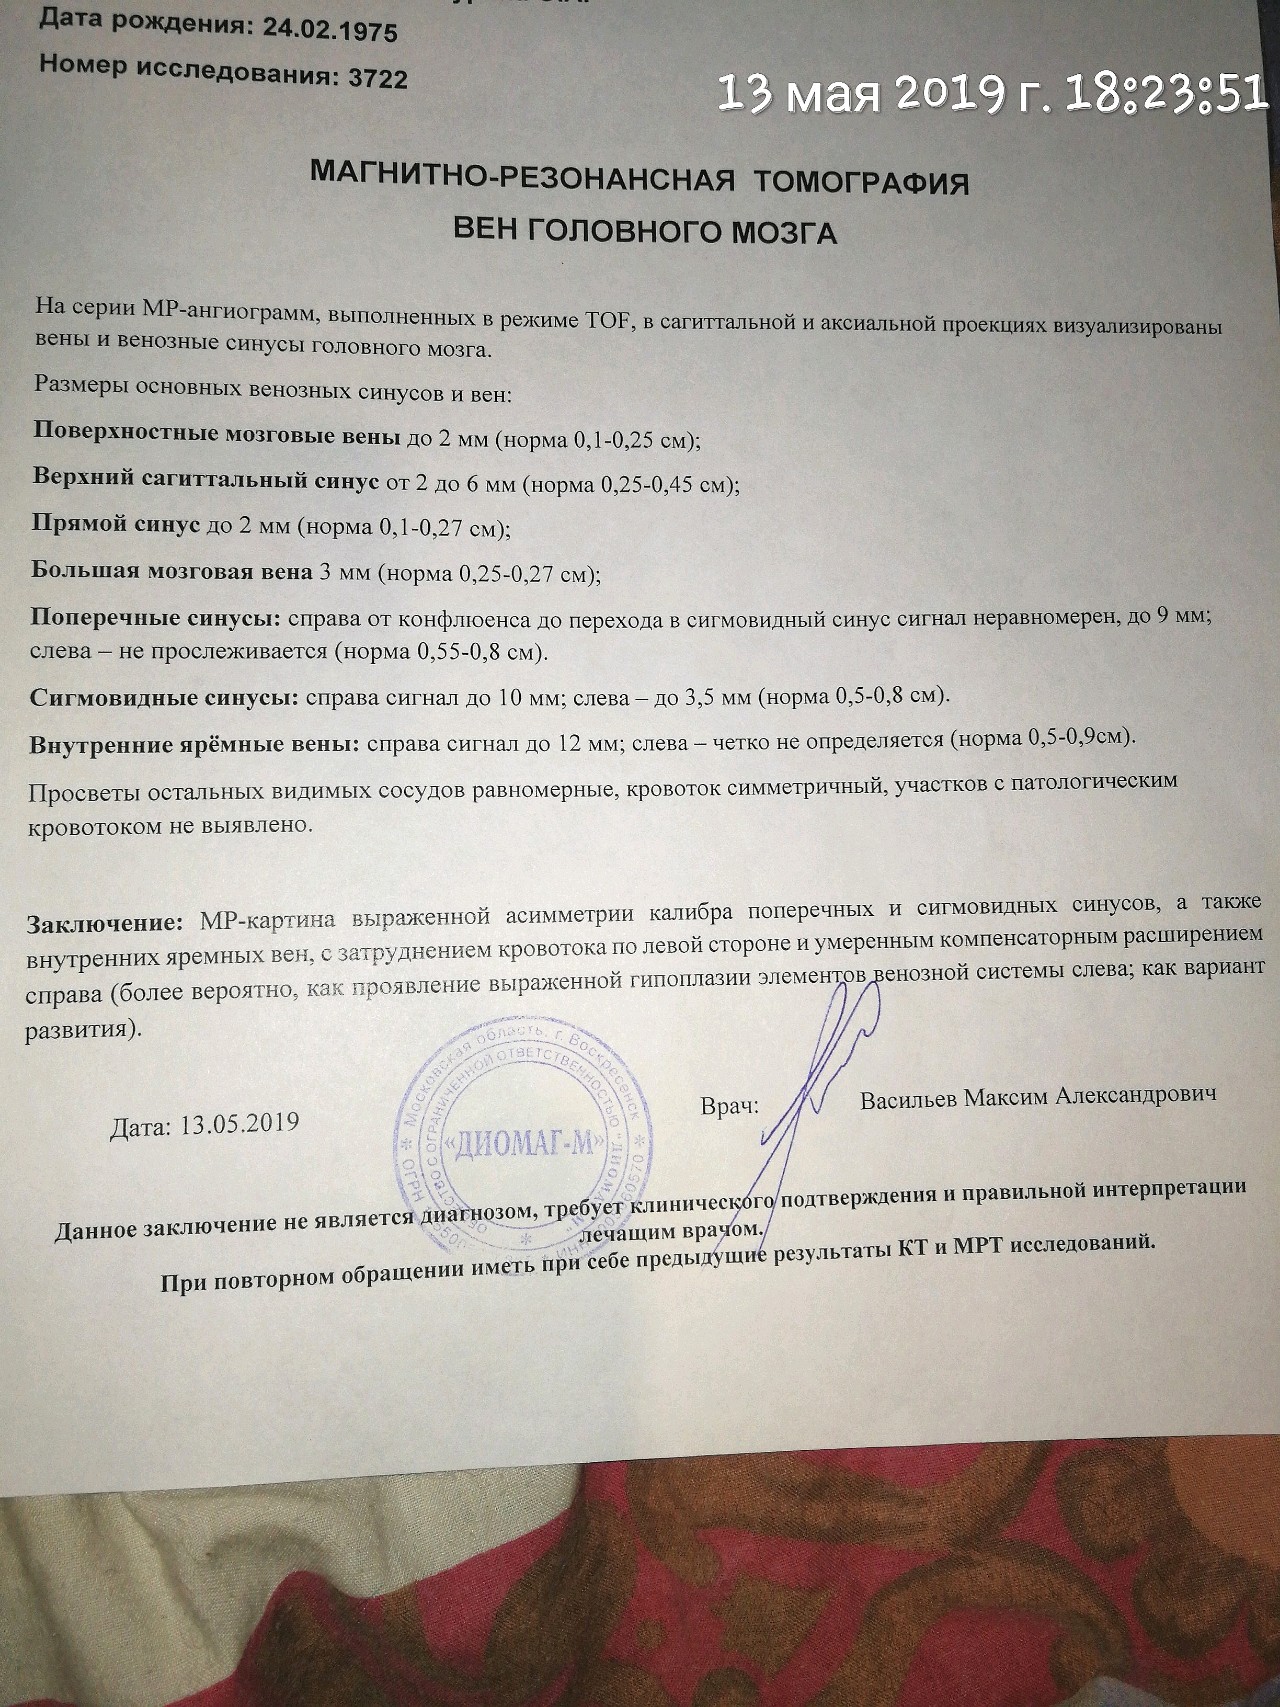

Медицинская диагностика: КТ и МРТ головного мозга